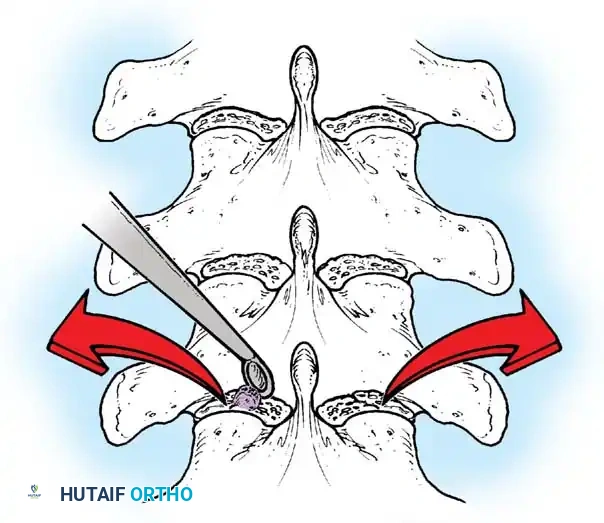

The Moe Technique (Thoracic Spine)

The Moe technique is a highly effective method for achieving intra-articular arthrodesis in the coronally oriented thoracic facet joints.

Fig. 38-26: The Moe technique of thoracic facet fusion, demonstrating the creation of hinged bone flaps.

- Expose the spine fully to the tips of the transverse processes.

- Using a sharp osteotome or Cobb gouge, begin a cut over the cephalad articular process at the base of the lamina.

- Carry this cut along the transverse process almost to its tip. Bend this cortical fragment laterally so it lies between the transverse processes, ideally leaving it hinged on its lateral periosteal attachment to preserve local vascularity.

- Thoroughly denude all articular cartilage from the superior articular process using a sharp curet.

- Make a secondary cut in the superior articular facet, working medially to laterally, producing another hinged fragment.

- Pack the resulting intra-articular defect tightly with cancellous bone graft.